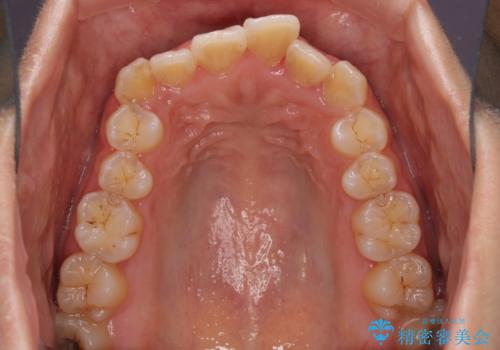

前歯のデコボコをインビザラインでスッキリと

- 上下前歯のデコボコを気にして来院された患者様です。

デコボコを解消する過程で、歯列の拡大により口元が突出する可能性があったため、4本の親知らずを抜歯しておき、歯列全体が後方に移動するように設計し、インビザラインにて矯正治療を行うこととしました。

日々の装着時間をしっかりと守って治療の臨んでくださったため、治療前のシミュレーションに近い形で矯正治療を進めて行くことができました。